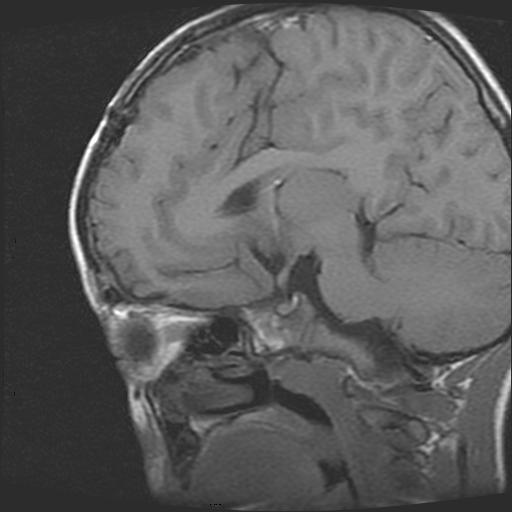

6岁小儿,左侧视神经瘤术后。现左侧视力减退。